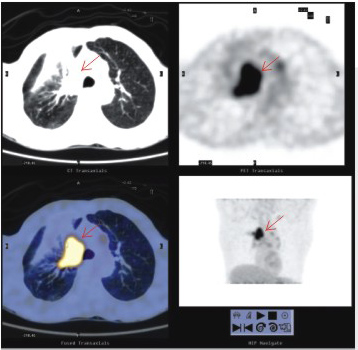

患者男性,76歲。5年前,PET-CT體檢發(fā)現(xiàn)右肺上葉微小高代謝灶,術(shù)后證實(shí)為早期肺癌。現(xiàn)患者全身情況正常,實(shí)現(xiàn)了腫瘤的早期診斷與根治。

2、 良、惡性鑒別及尋找原發(fā)灶和轉(zhuǎn)移灶

PET-CT顯像作為功能顯像,能夠揭示機(jī)體細(xì)胞代謝的異常變化,因而能較容易鑒別腫瘤是良性還是惡性;而PET-CT顯像能同時(shí)獲得PET與CT兩者的全身的斷層圖像,對于腫瘤原發(fā)灶與轉(zhuǎn)移灶的診斷尤為有利。

肺癌合并炎癥及遠(yuǎn)端肺不張 | 胃癌多發(fā)肝轉(zhuǎn)移 |